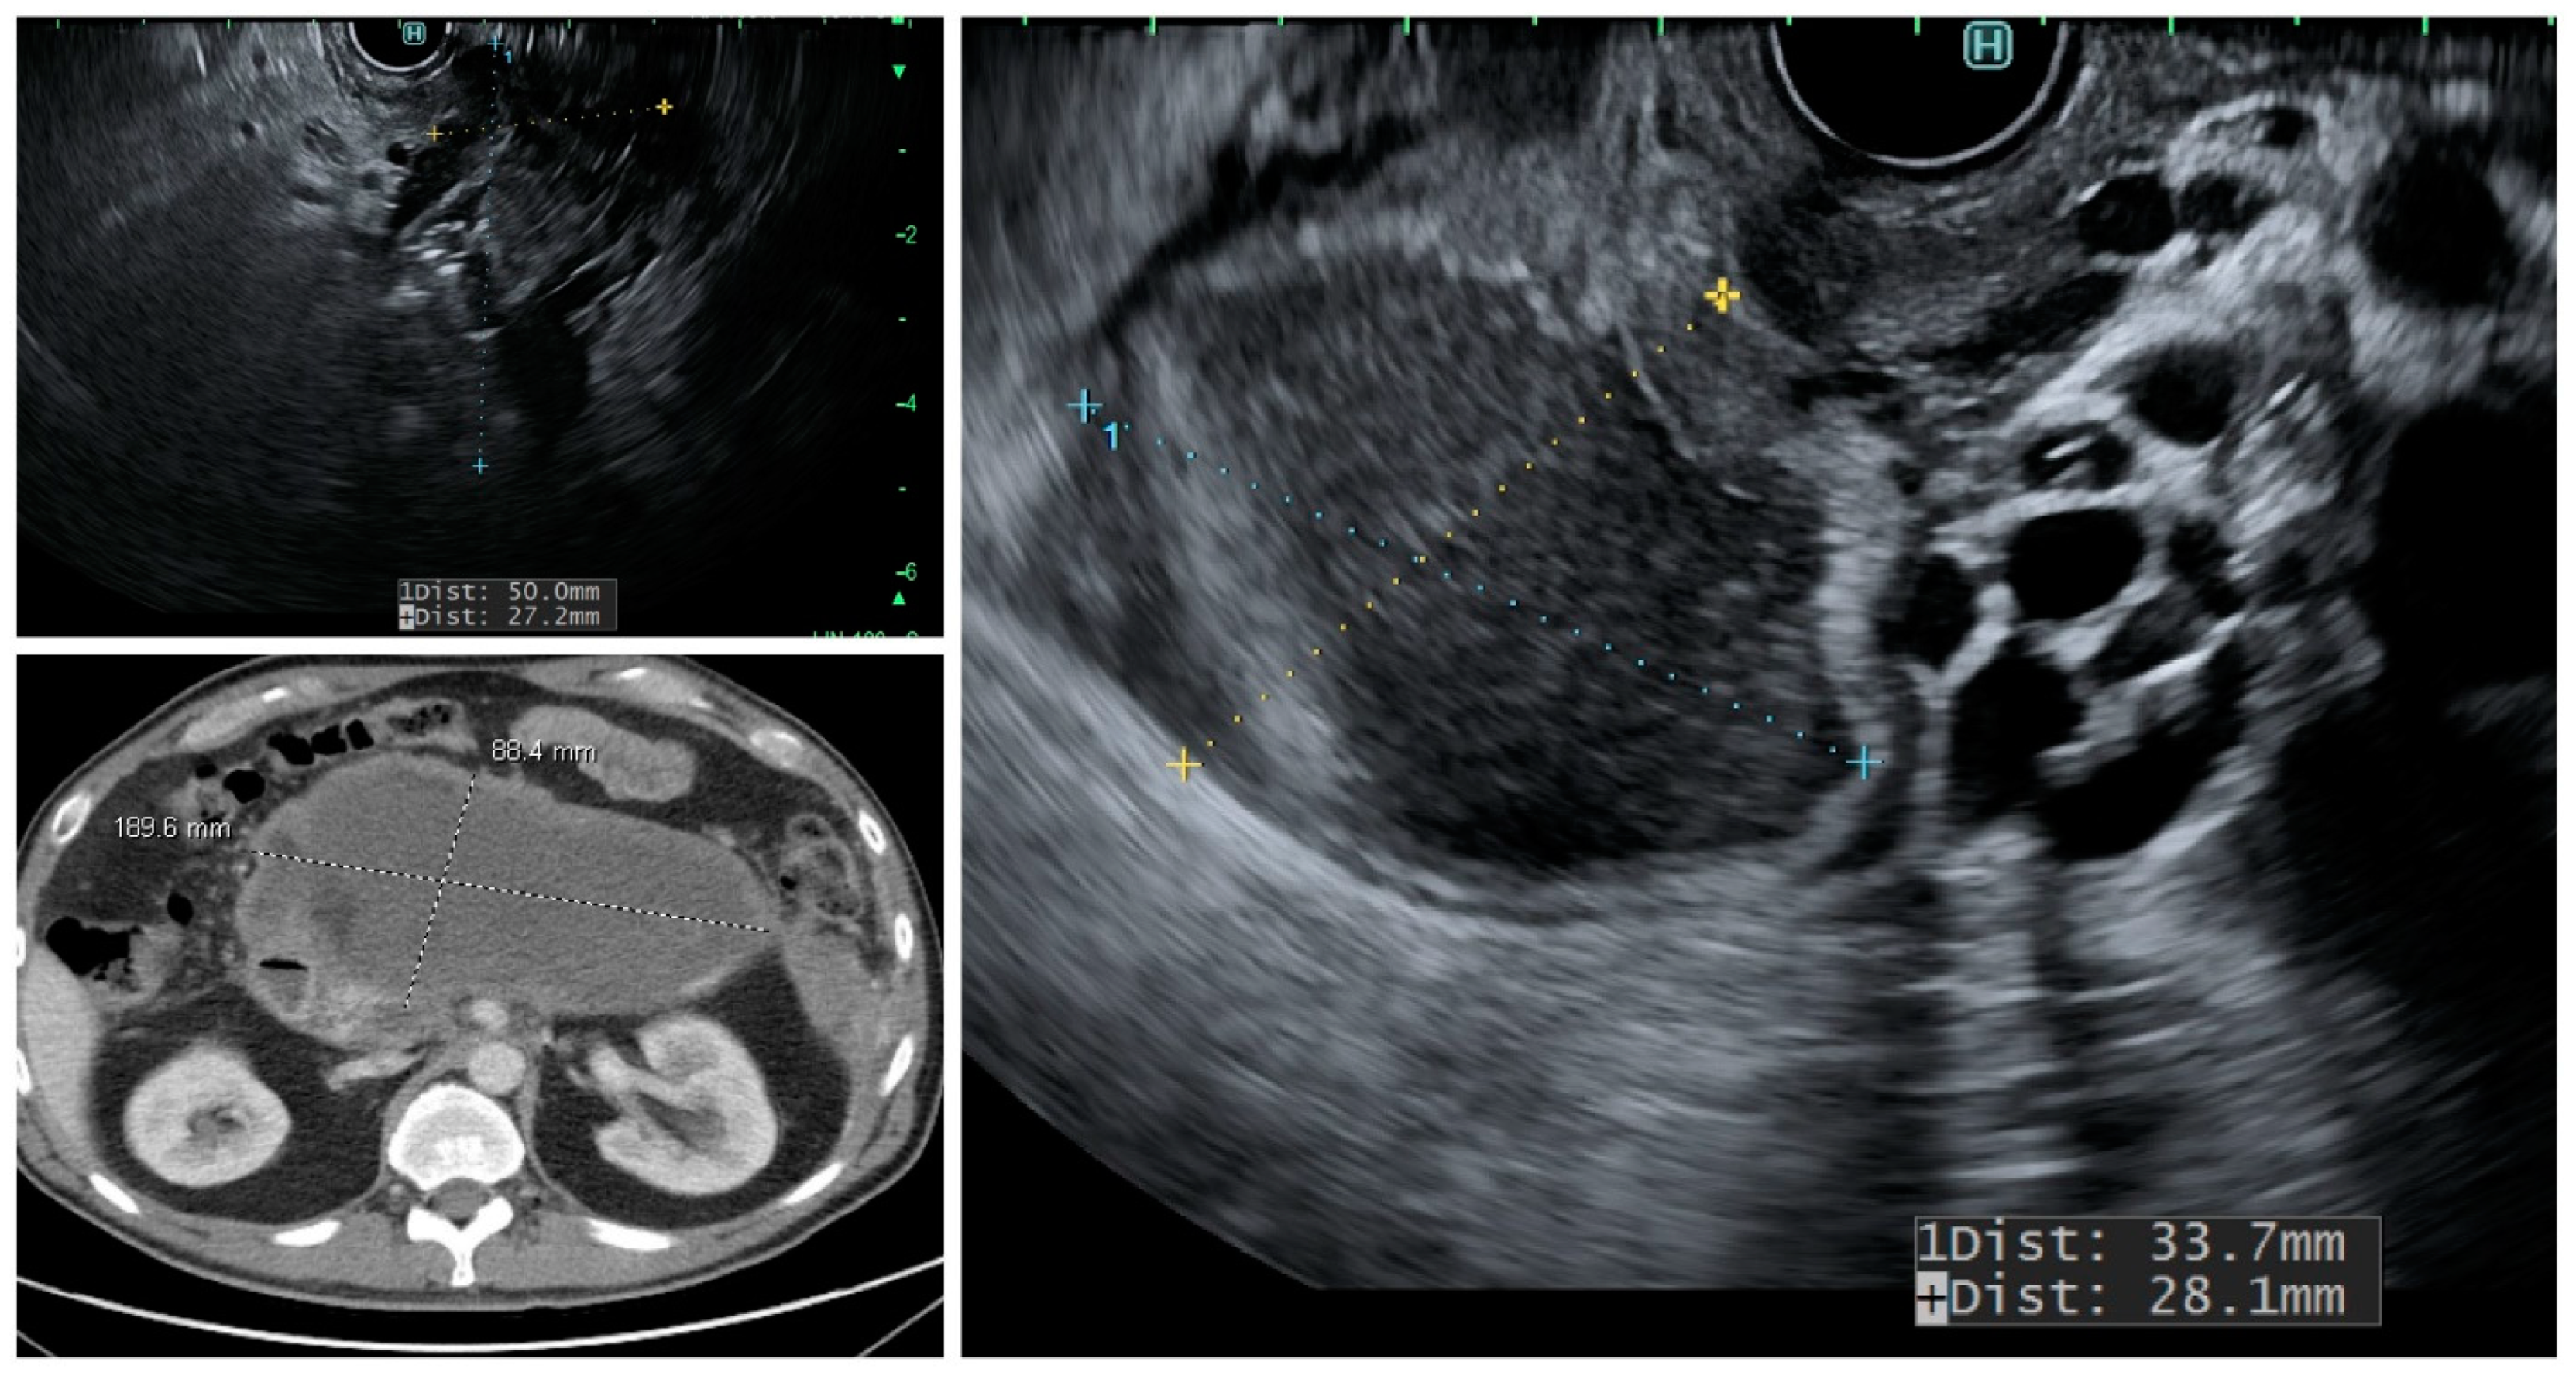

Figure 1.

Endoscopic ultrasound and CT scan images showing pancreatic pseudocyst near the uncinate process.

The above classifications are based on the pathologic examination of the resected PC. Imaging modalities and the analysis of PC fluid can provide a clue towards identifying cyst types; however, the degree of dysplasia and its malignant potential can still be uncertain. Most non-neoplastic pancreatic cysts are pseudocysts (Figure 1) and are seen following acute pancreatitis or are associated with chronic pancreatitis.